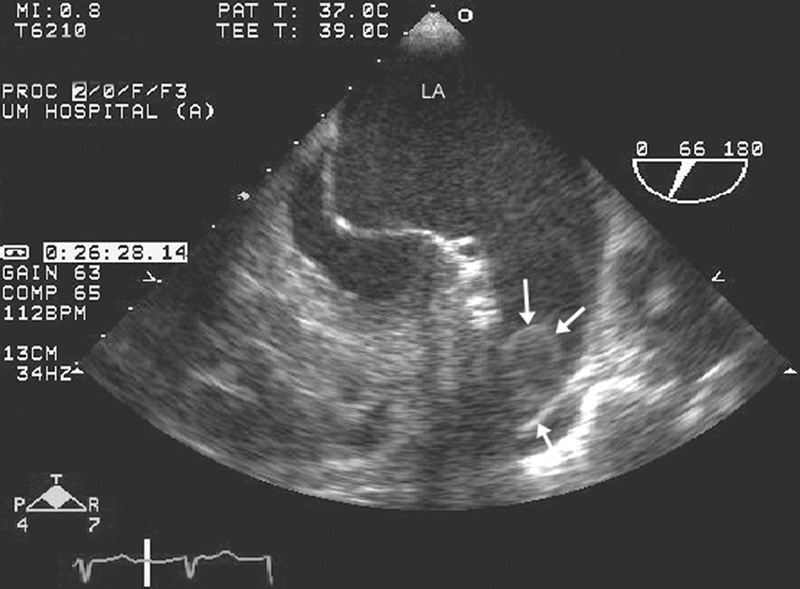

فحوصات تشخيصية لبعض امراض القلب والشرايين التاجية